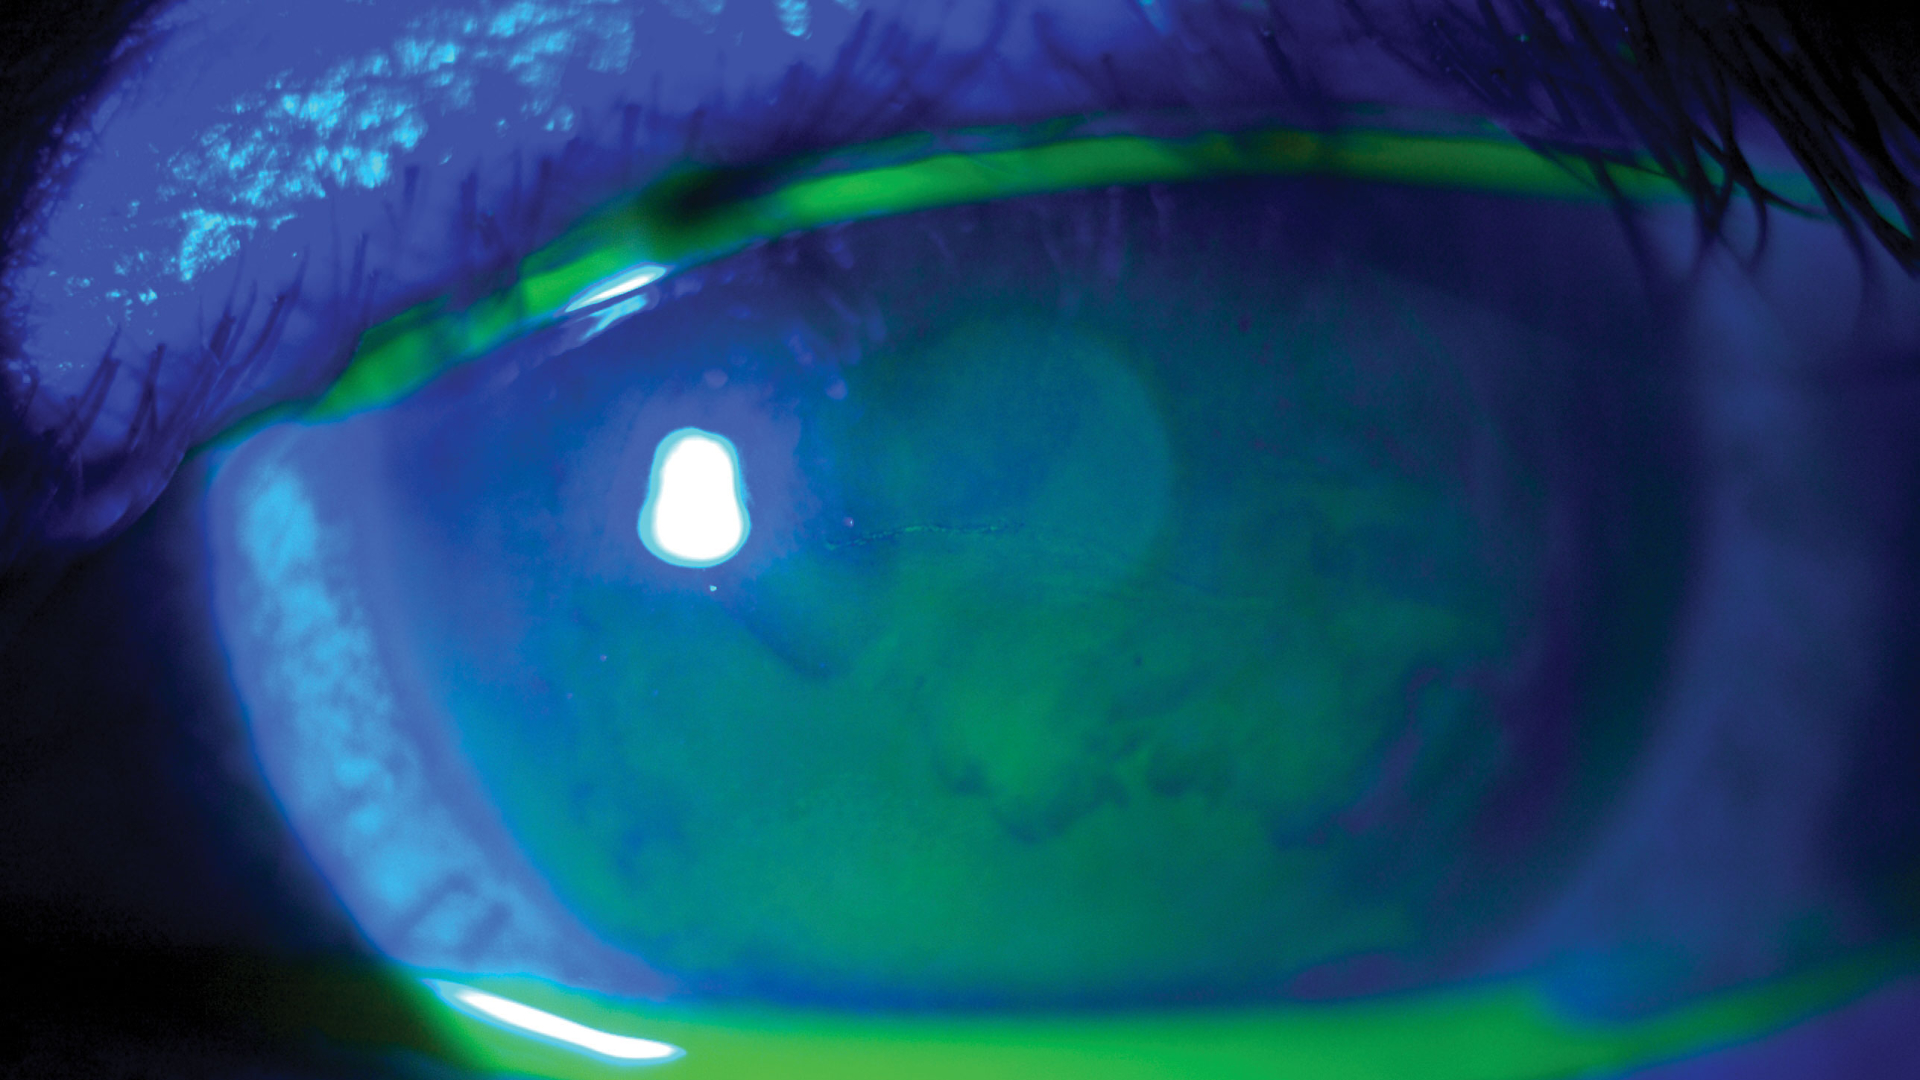

Göz Kuruluğu Tedavisi

Korneal Topografi